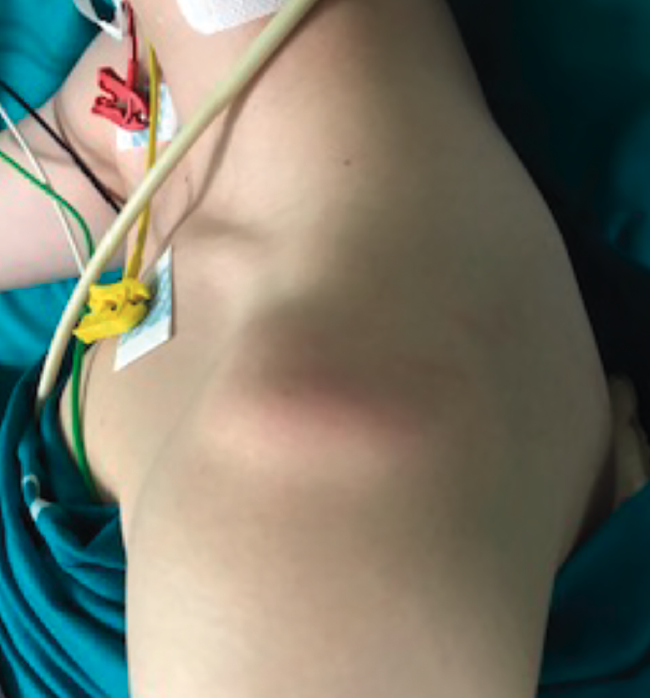

Small Hill-Sachs lesions (HSLs) in AP projection are only visualized with the shoulder in internal rotation (Figure 5A and B), while larger lesions can be seen in both internal rotation and external rotation(20) - the axillary projection affording better visualization of HSLs, however. For assessing glenoid bone loss, it is advisable to use an axillary projection or modified Bernageau projection, with a sensitivity and specificity of over 90%(20,21).

Figure 5. A and B: two cases of patients with Hill-Sachs lesions. A: comparison showing that it is easier to visualize the defect with the shoulder in internal rotation, especially in the case of a small defect; B: the same Hill Sachs lesion is observed on a comparative basis in the plain radiograph and MRI scan; C: computed axial tomography (CAT) view of a reverse Hill-Sachs lesion; D: ALPSA type lesion in conventional magnetic resonance imaging (MRI) and arthro-MRI. The latter technique is useful in the event of diagnostic doubt, since it offers more precise information about the type and characteristics of the capsulolabral lesion.

If these bone lesions are visible on plain radiographs, they can be assumed to be of considerable size; a CAT study therefore would be indicated to quantify the defect.

Three-dimensional reconstructions afford valuable information about the morphology of the glenoid cavity, as well as precise measurement of the size, location and depth of the defects of the humeral head (Figure 5C) and glenoid cavity(19,22) - these being decisive factors for the planning of surgery.

Arthro-MRI with intraarticular gadolinium contrast offers greater sensitivity and specificity in the diagnosis of lesions of the labrum than conventional MRI without contrast injection(19), though it is not a necessary routine test provided the MRI images are analysed by an experienced professional. It is reserved for those cases in which conventional MRI poses doubts (Figure 5D), or in patients with postsurgical relapse.